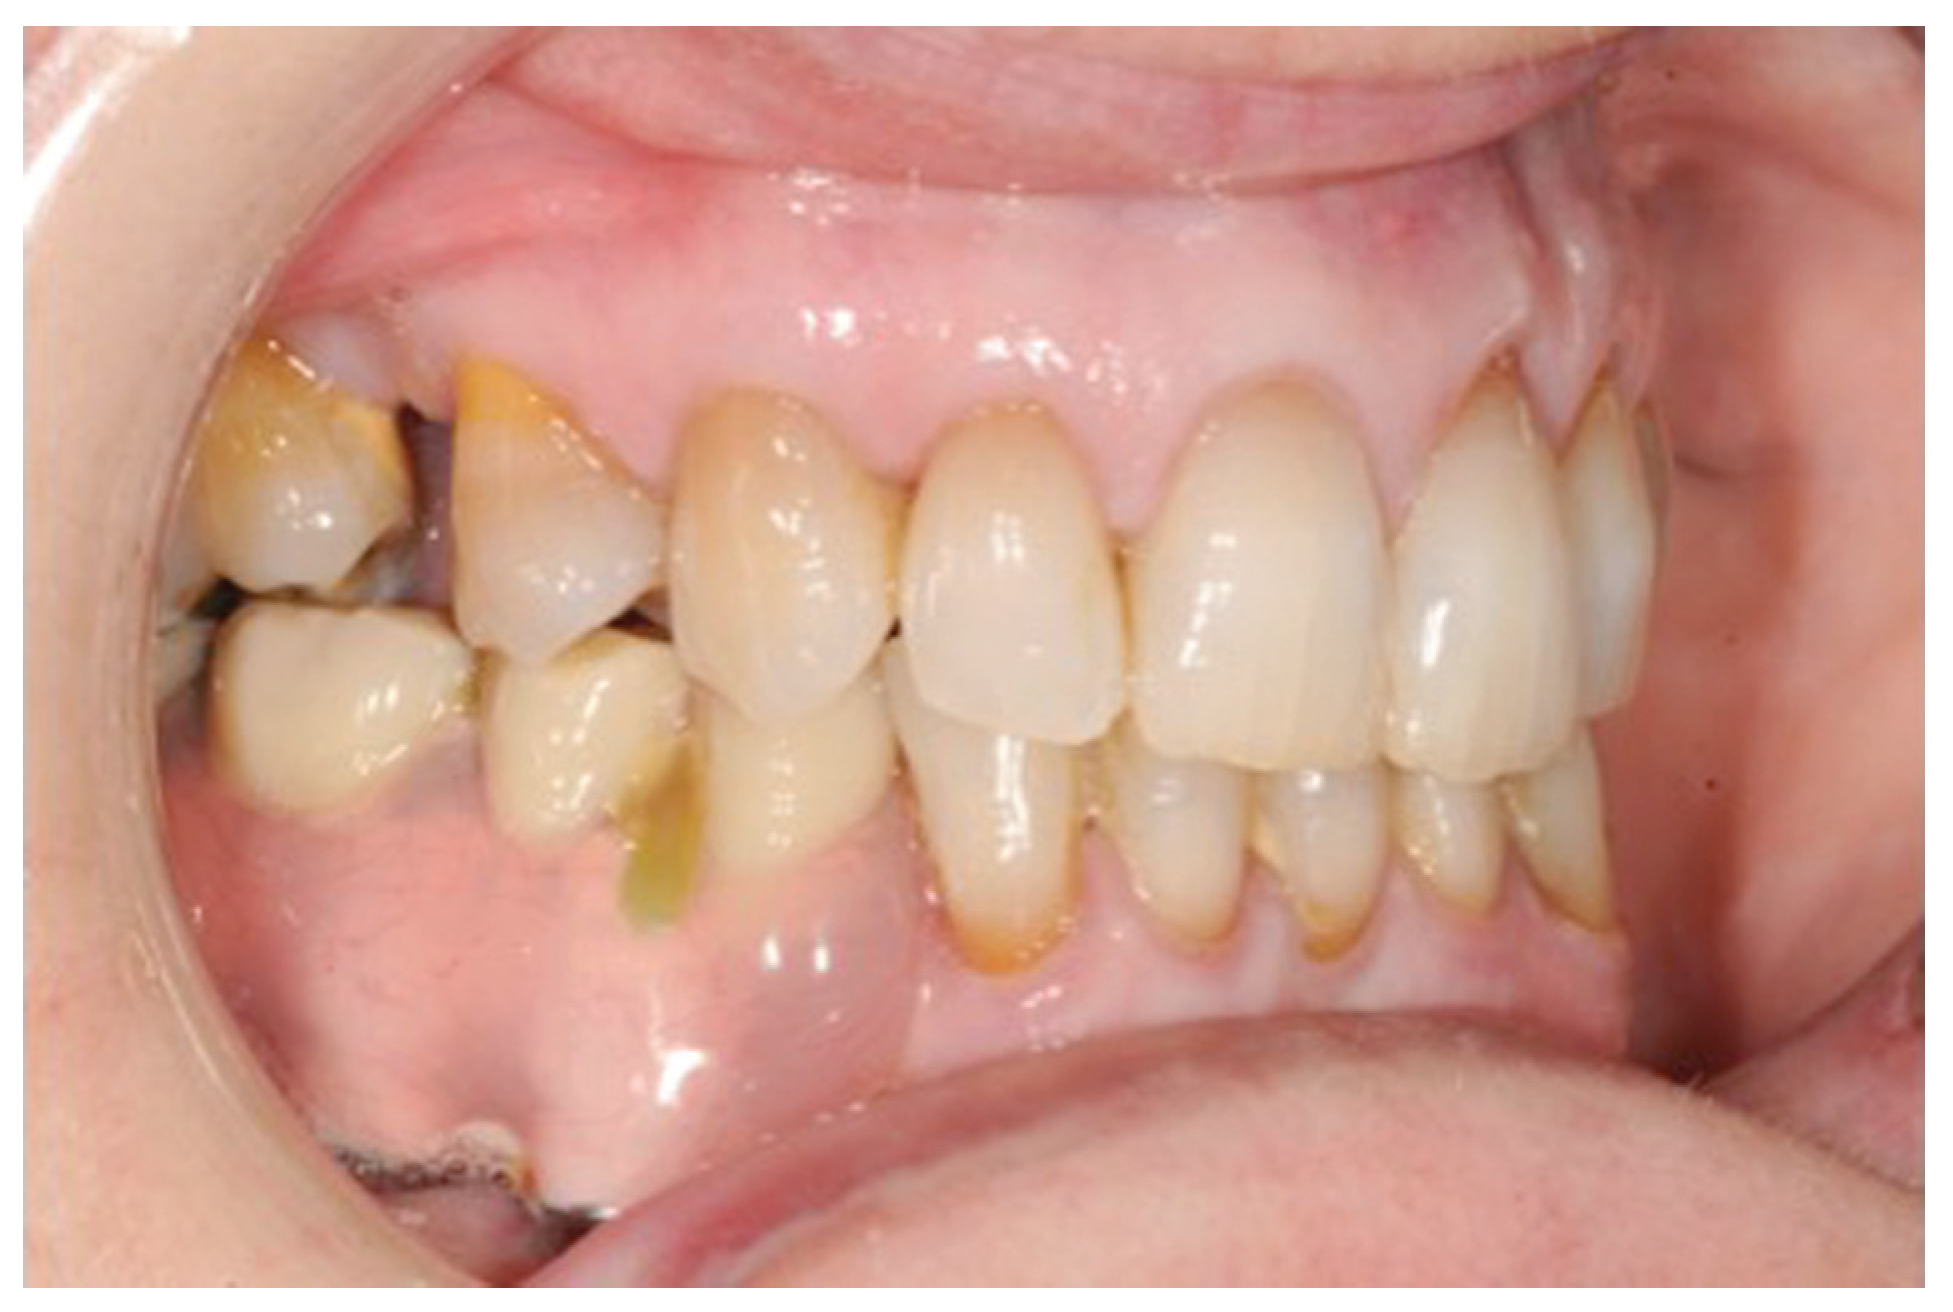

Figure 7.

Dental rehabilitation of the patient.